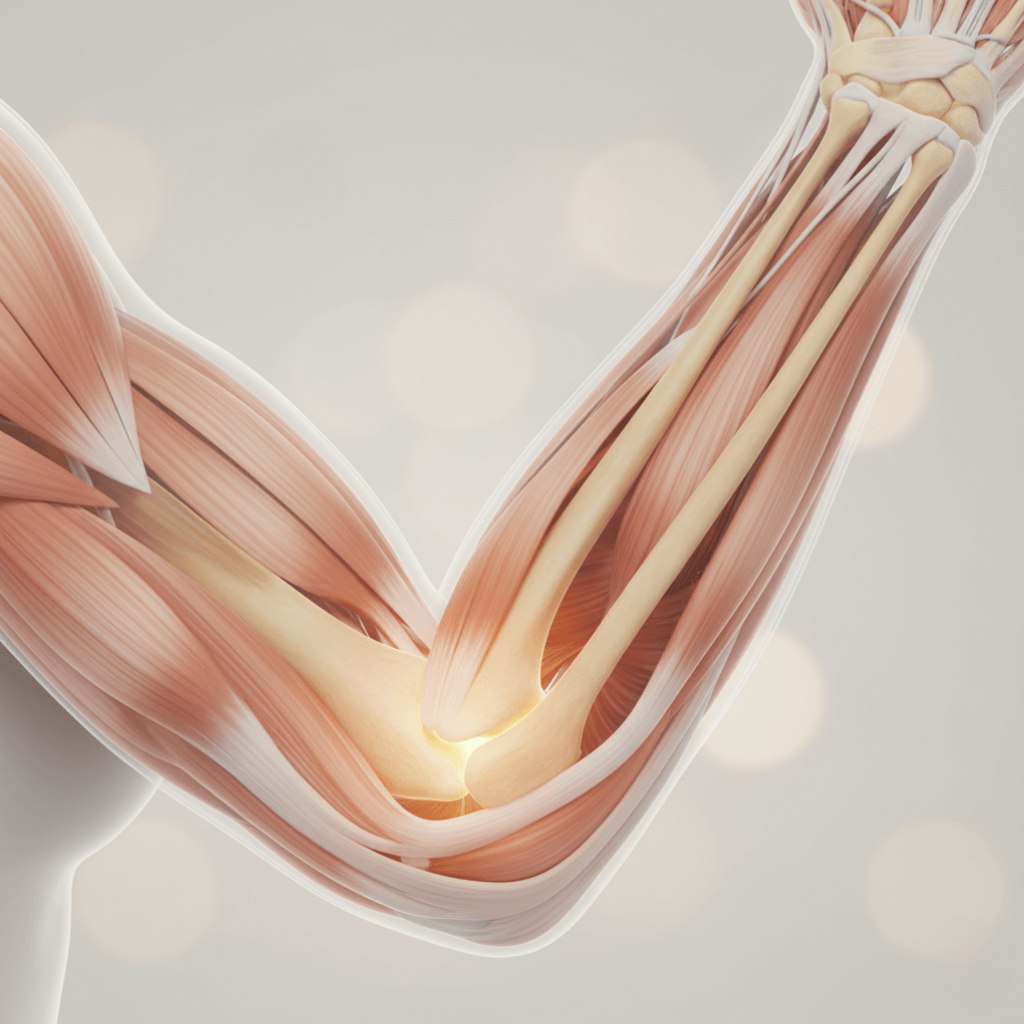

The Importance of Joints in Daily Life

Joints are essential for almost every movement we perform daily.

They connect bones, allow flexibility, and absorb impact, ensuring we can walk, run, climb stairs, stretch, and participate in physical activities safely.

When joints are healthy, mobility is preserved, which directly affects energy, disposition, and overall quality of life.

Stiff or uncomfortable joints can limit independence, make simple tasks difficult, and even affect emotional well-being.